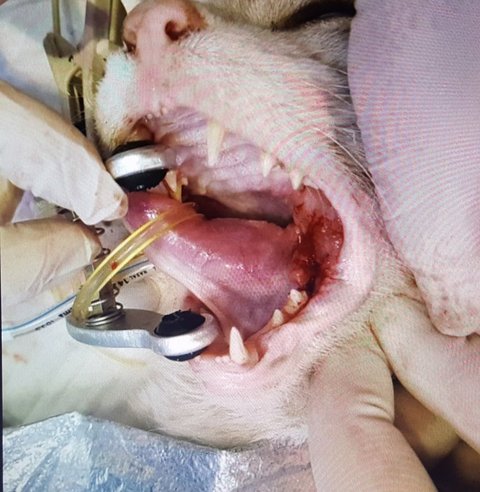

위의 사진은 점박이가 수술 받는 모습입니다.

점박이는 구내염으로 인한 고통으로 먹지를 못해서 뼈가 앙상할 정도로 야위어 있었습니다.

희망이를 검진하고 있는 모습입니다.

보통은 마취를 하지 않고서는 이렇게 검진할 수 없는데 아이가 워낙 순둥이라서 가능합니다.

희망이는 작년부터 이미 구내염을 앓고 있었음에도 제가 미처 제대로 관찰하지 못해서

상당히 악화된 상태로 제대로 먹지를 못해서 뼈만 앙상하게 남은 상태 입니다.